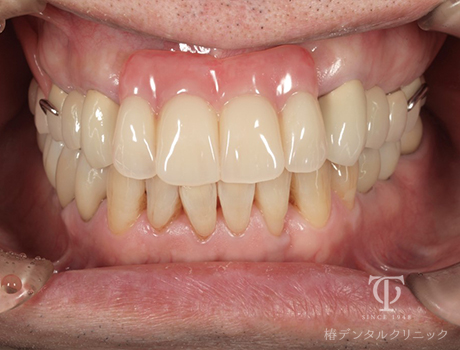

正面観AGCテレスコープ義歯装着

- 症状

- 右上の痛み

- 治療期間

- 約1年半

- 治療費用

- (上顎)インプラント治療:473,000円×2

(上顎)AGCテレスコープ義歯:1,500,000円

(下顎)インプラント治療:473,000円×2

右上の歯が痛いということで来院されました。インプラントとAGCテレスコープという方法でかみ合わせを再構築しました。

【リスク・副作用】

インプラント治療後、痛みや違和感、出血、腫れなどが出る事があります。喫煙者、糖尿病などの方の場合、歯が生着しない場合があります。入れ歯を清潔に保たないと虫歯や歯肉炎、歯周病になるリスクがあります。